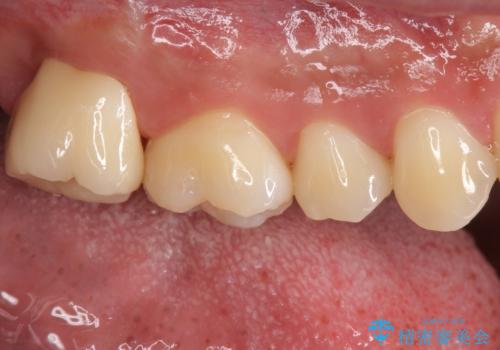

銀歯をなくしたい ジルコニアクラウンでの修復

- 右上7 仮歯+ジルコニアクラウン:11,000円+121,000円費用は治療当時の料金となります

ブラッシングが上手な患者様であったため歯茎の締りもよく、大変適合の良い被せ物を装着することができました。